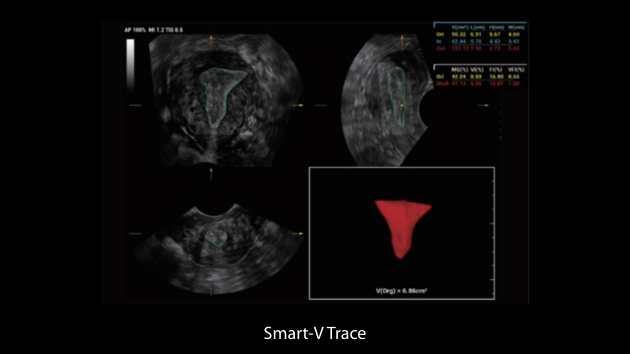

Nuewa I9, kad?nlara ve yenido?anlara y?nelik sa?l?k hizmetleri i?in ?zel olarak tasarlam??t?r ve i?ten d??a yenilik?i bir deneyim sunmaktad?r. Bu yenilikler, karma??k klinik senaryolara ili?kin derinlemesine bilgilere dayal? olarak geli?tirilmi?tir ayr?ca do?ru ve zaman?nda yan?tlar?n yan? s?ra, ola?an├╝st├╝ verimlilik ve ola?an├╝st├╝ kullan?c? deneyimi sunar.